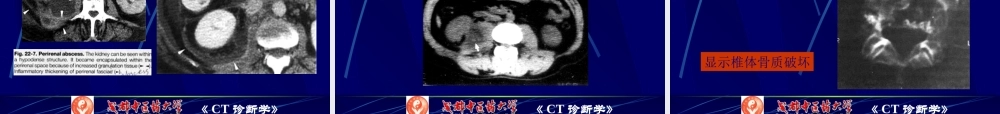

《CT诊断学》腹膜腔和腹膜后腔CT检查第一页,共七十九页。《CT诊断学》检查方法正常解剖腹膜腔:壁层和脏层腹膜之间的腔隙,女性经输卵管与外界通。腹膜:覆盖腹、盆腔壁及脏器外表的浆膜,有壁层和脏层之分,由间皮和结缔组织构成。第二页,共七十九页。《CT诊断学》第三页,共七十九页。《CT诊断学》冠状面第四页,共七十九页。《CT诊断学》横断面第五页,共七十九页。《CT诊断学》•网膜—脏层腹膜由器官移行于另一器官,如大网膜、小网膜。•大网膜—由胃移行于横结肠,呈围裙状,自胃大弯和横结肠向下悬垂复盖小肠。共4层腹膜。内含脂肪、血管、淋巴管和神经。其上皮细胞有吸收和保护机能,移向炎性病变形成包裹病灶以限制炎症蔓延。第六页,共七十九页。《CT诊断学》•小网膜—肝与胃、十二指肠移行的双层腹膜,与肝静脉韧带相连。与肝下胃后、横结肠、后腹壁围成小网膜囊经温氏孔与腹膜腔相通。第七页,共七十九页。《CT诊断学》•系膜—连接腹后壁•和肠管的腹膜•小肠系膜—呈•扇形由左上〔腰2〕•向右下斜跨止于右骶髂关节,将•腹腔分为左右两部。•阑尾系膜—回•肠末端与阑尾间的腹膜皱襞,近似三角形。•横结肠系膜;•乙状结肠系膜第八页,共七十九页。《CT诊断学》•韧带:•是腹膜壁层移行于器官的一种皱襞,如左右膈结肠韧带、肝镰状韧带、肝冠状韧带。•或是腹膜由一个器官移行于另一个器官的腹膜皱襞,如肝肾、胃膈、胃脾、脾肾、膈脾、肝结肠、十二指肠肾、肝胃等韧带。第九页,共七十九页。《CT诊断学》•腹膜腔的分隔•横结肠系膜将其分隔为上下两腔;下部又被斜行的小•肠系膜分为左右两腔,右下界为小肠系膜与升结肠的交•界处,左侧可与盆腔相通。•膈下间隙—右膈下间隙为膈与肝右叶之间,内侧为•肝镰状韧带,后界为肝冠状韧带。左膈下间隙为膈•与肝左叶、胃及脾之间,右为肝镰状韧带,后为肝•的左三角韧带。•肝下间隙—肝下的后局部为肝肾隐窝或Morrison氏囊,•CT扫描是肝下间隙最低处。左肝下间隙的外部为小网•膜囊。第十页,共七十九页。《CT诊断学》•小网膜囊—位于小网膜、胃、十二指肠和胃•韧带前方,通过Winslow孔与腹腔通,Winslow•孔边缘内有门静脉、胆总管和肝动脉。•结肠旁沟—右结肠旁沟在升结肠外缘与腹壁•间,上与右膈下,肝下间隙通;左结肠旁沟在•降结肠外缘与腹壁间,仅向下经左髂窝与盆腔•通。•膀胱直肠陷窝—是腹膜腔最低处。第十一页,共七十九页。《CT诊断学》•腹膜后腔〔前已描述...